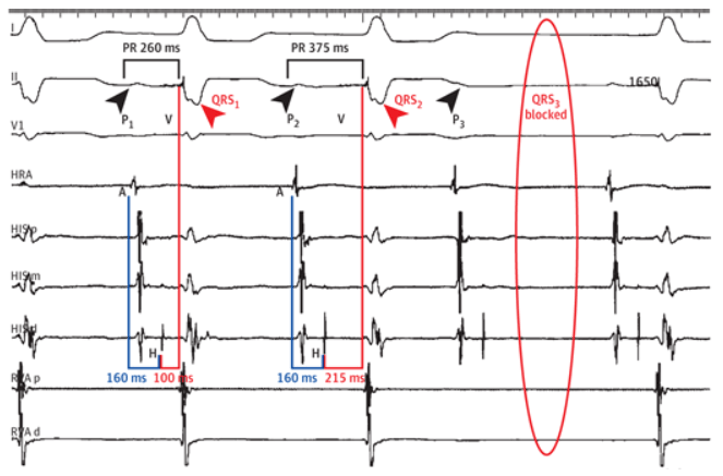

Location of block

What is infra-Hisian conduction disease?